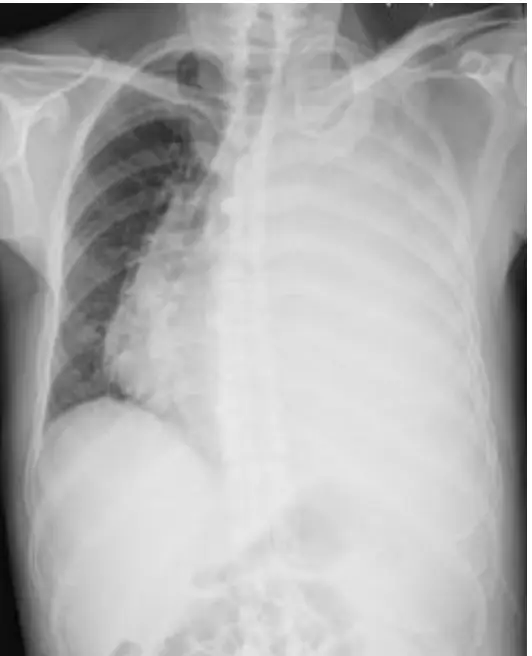

圖(五)(甲病人)

• 左側全葉均呈均質放射不透光(opaque),左橫膈輪廓被完全遮蔽,左側肋膈角消失。

• 明顯可見縱隔結構(心影、氣管)向右側推擠移位。

– 右移代表左側胸腔內正壓增加,典型為大量液體積聚於胸膜腔中,形成 massive pleural effusion,並壓迫肺組織。(pmc.ncbi.nlm.nih.gov)